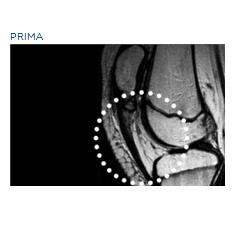

Las aplicaciones más comunes de la TERAPIA DE ONDA DE CHOQUE son el tratamiento de los dolores musculoesqueléticos crónicos resultantes de tendinopatías,puntos gatillo, eliminación de calcificaciones y estimulación de no uniones óseas.